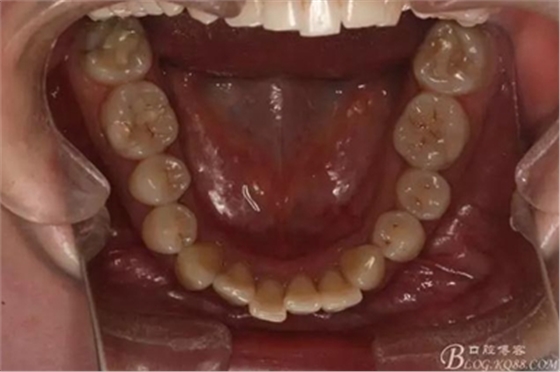

患者,女,主訴:牙齒不齊。

如圖,該病例為簡單排齊病例,但77鎖合是矯治中的關(guān)鍵所在,你會怎么處理?